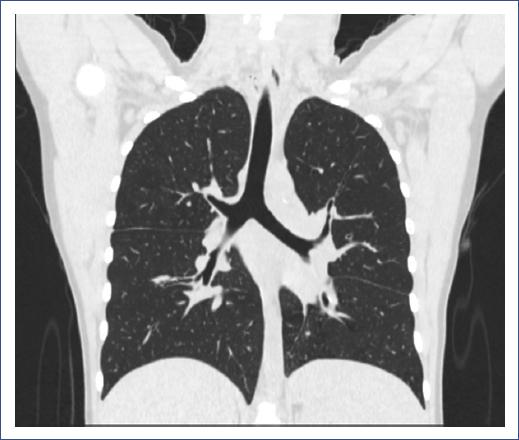

At 9 months of age, she required hospitalization for pneumonia and presented with recurrent respiratory tract infections from the age of 4. From the age of 8, she had prolonged cough and purulent rhinorrhea and was diagnosed with bronchiectasis by computed tomography (CT) of the chest at 11 years old, which persisted in the most recent CT (Fig. 1).

Figure 1 Computerized axial tomography at 17 years old, showing right upper solitary nodule, bilateral cylindrical lamellar atelectasis and bronchiectasis, left septal thickening, and axillary nodal hypertrophy.